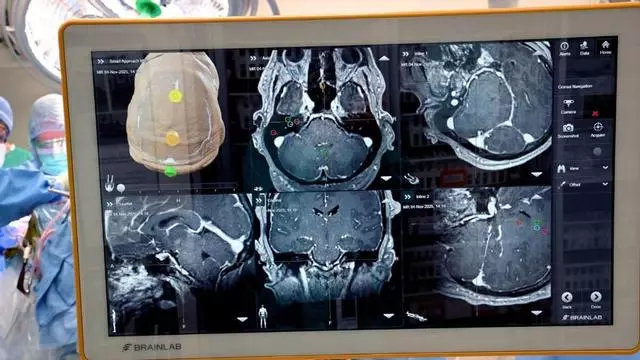

La operación abre una nueva vía para interpretar señales cerebrales en regiones vinculadas a funciones más complejas. / Crédito: Universidad de Colorado Anschutz.

Investigadores de la Universidad de Colorado Anschutz y UCHealth en Colorado, Estados Unidos, han realizado una cirugía que podría modificar el futuro de la neurotecnología: por primera vez, lograron implantar una interfaz cerebro-ordenador (BCI, por sus siglas en inglés) en zonas superiores del cerebro, y no en las regiones motoras primarias donde se habían concentrado la mayoría de los procedimientos previos.

Patterson se convirtió en el primer ser humano en recibir este tipo de implante en una zona cortical de mayor nivel funcional. La cirugía dejó instalados tres puertos en la parte superior de su cabeza, capaces de comunicar la actividad cerebral con ordenadores externos.